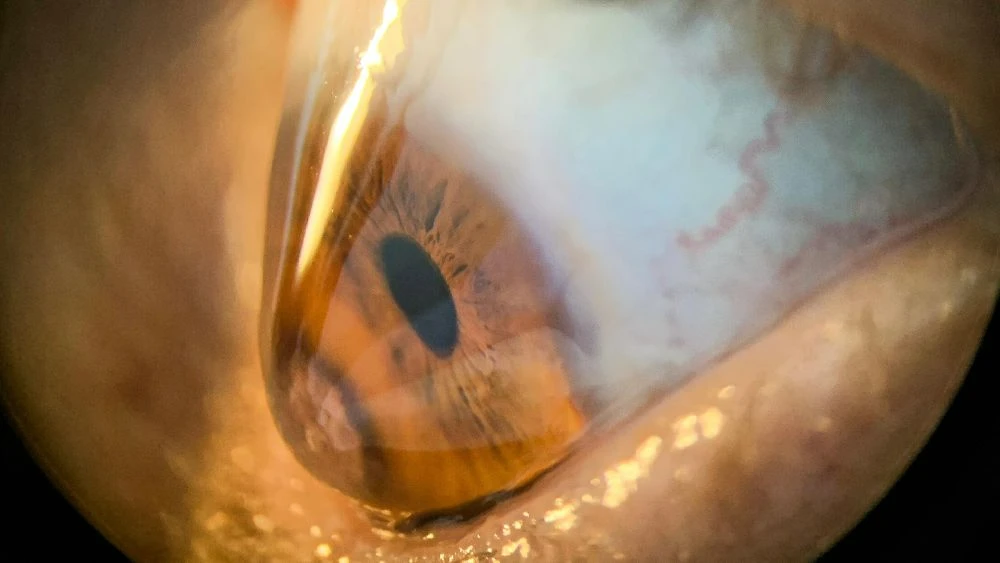

O ceratocone é uma doença da córnea que provoca afinamento e deformação progressivadessa estrutura, deixando-a mais curva e irregular. Essa alteração causa visão embaçada, distorcida e aumento frequente do grau,principalmente astigmatismo.

As principais opções de tratamento incluem: óculos (nas fases iniciais), lentes de contatoespeciais, crosslinking (indicado para progressão), anel intracorneano e transplante decórnea em casos mais avançados.

O ceratocone é uma doença da córnea em que ela fica mais fina e assume um formato irregular, parecido com um cone. Isso causa visão borrada, distorcida e dificuldade para enxergar.